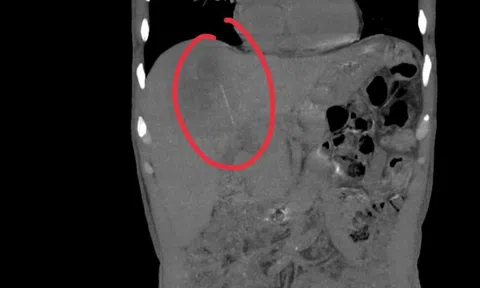

Bác sĩ thăm khám cho bệnh nhân bị chó cắn. Ảnh: BVCC.